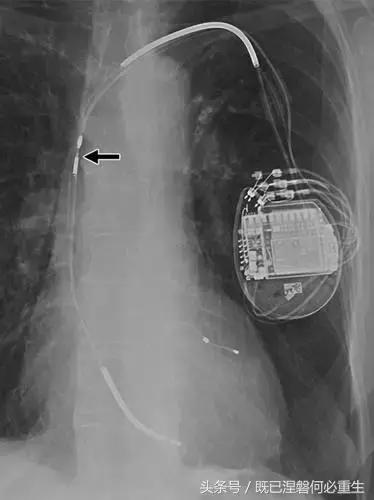

图。 7A 79岁的男性患有电极折断和迁移。

A,初始胸前X线片显示Pacesetter双腔起搏器低于锁骨的心房导线不完全断裂(变薄)(箭头)。

图。 7B 79岁的男性患有电极折断和迁移。

B,大约3年后,电极完全断裂,金属传导碎片(箭头)分离。 远端片段(箭头)已经偏移尾侧,但是由于围绕电极的射线可穿透鞘的束缚效应而没有迁移到肺循环中。 引线和中心静脉导管最常见于锁骨和第一肋骨之间断裂,因为它们在臂运动期间被锁骨下肌肉或腱或肋锁韧带压缩[16]。

造成设备故障的最常见的X光检查原因之一是铅断裂。锁骨下静脉经过锁骨下的部位是骨折最常见的位置[16](图7A和7B)。在这个位置的损伤可能发生在导管或导线,并已被描述为锁骨下夹断综合征和锁骨下压溃综合征[16?18]。临床上,骨折的导线通常在患者中产生可以是连续的,间歇的或依赖于患者定位的症状。识别这些状况可能需要挑衅性的动作,例如等长臂锻炼,仰卧或侧向定位或Valsalva。设备检查将显示异常的起搏阻抗(如果绝缘破裂允许导体暴露则减小,如果导体断裂但绝缘完好则增加),感测错误和起搏捕获损失[12]。导线断裂或绝缘损坏可能导致感测或起搏异常。对心律失常的不适当的过感知或欠感应可能导致不适当的治疗,例如抗心动过速起搏和休克治疗,或不适当的抑制治疗。